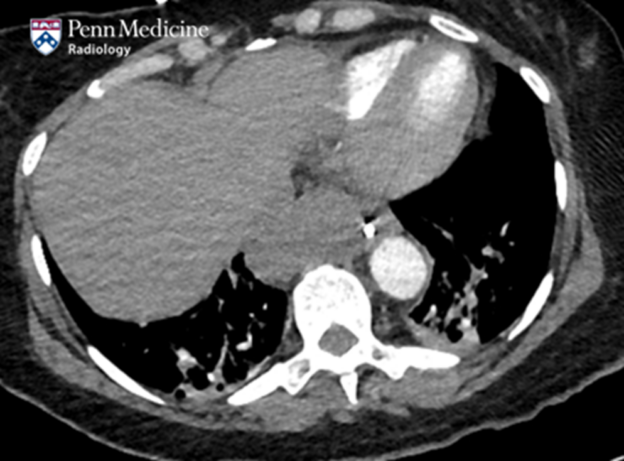

60-year-old man with thoracic mass

A 60-year-old man undergoing inpatient treatment for pneumonia was transferred to a tertiary care center for the management of a thoracic mass.